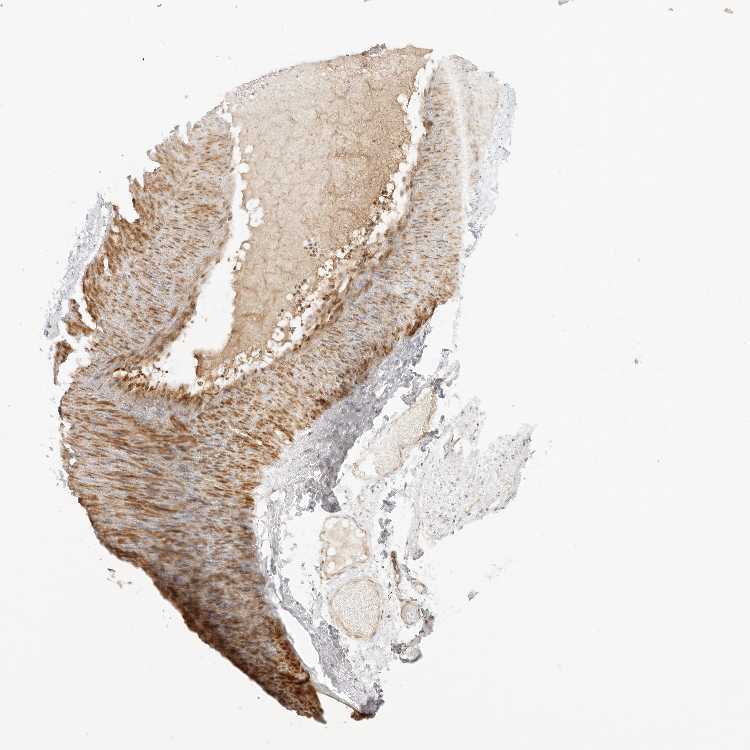

SOFT TISSUE 2 - Antibody stainingi

Antibody staining in the annotated cell types in the current human tissue is reported as not detected, low, medium, or high, based on conventional immunohistochemistry profiling in selected tissues. This score is based on the combination of the staining intensity and fraction of stained cells.

Each image is clickable and will lead to virtual microscopy that enables deeper exploration of all samples and also displays staining intensity scores, fraction scores and subcellular localization as well as patient and tissue information for each sample.

Antibody HPA027804Antibody HPA027805Antibody HPA027806Antibody CAB009320

Fibroblasts Not detectedNot detectedNot detectedMedium

Peripheral nerve Not detectedNot detectedNot detectedNot detected